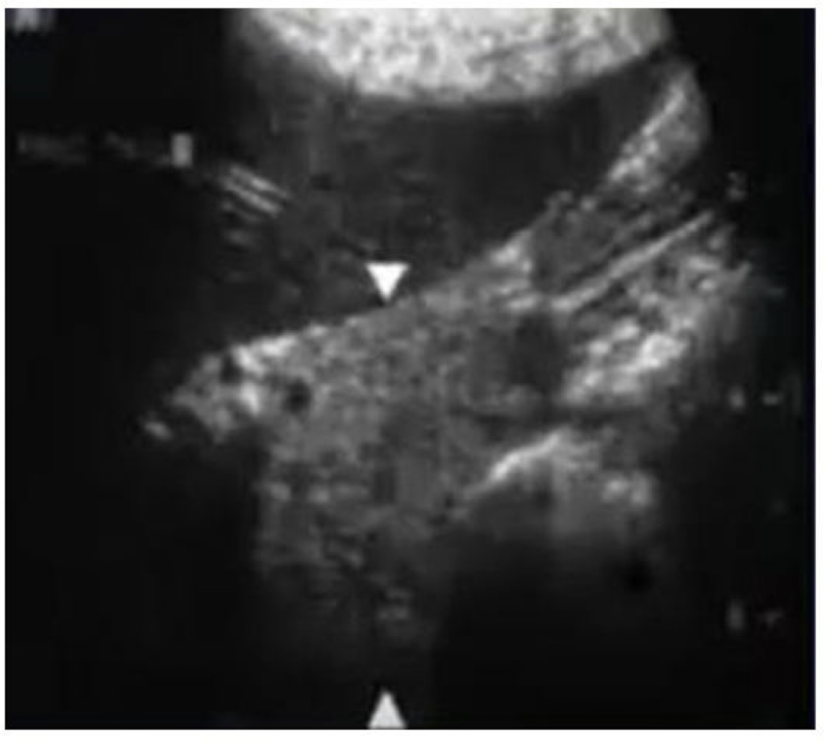

Look over this image

We look for the vessels to find the pancreas

label this image

label